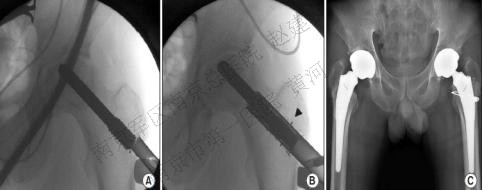

带血管蒂大粗隆移植骨(greater trochanter vascularized graft,GTVG):清除死骨后将带有旋股外侧动脉横支的大粗隆移植骨自头颈交界处开窗植入。Zhao对191例患者随访8年,最终只有23例患者再次行全髋置换,118例患者病情未见进展。

A DSA显示旋股外侧动脉穿支;B)DSA显示股骨头供血不足,但旋股外侧动脉穿支状态良好;C)术后DSA显示带有旋股外侧动脉穿支的大粗隆已植入股骨头内;D)DSA显示股骨头内血管再生。

游离腓骨移植(free vascularized fibular graft,FVFG):侧卧位,前外侧弧形入路,解剖分离出旋股外侧动脉升支及伴行静脉,C臂机监视下自股骨近端外侧向颈内制备骨隧道,移除死骨,显露同侧腓骨,将带有腓动静脉血管的腓骨游离,植入骨隧道中,吻合血管。Judet对60例患者进行了18年的随访,仅52%效果良好,但40岁以下患者的成功率可达80%,Ficat II期、III期的成功率也能达80%,提示病人的选择对治疗效果的影响;Urbaniak也持相同看法,其224例患者中,Ficat I和II期的成功率达到88%,而III期和IV期患者的成功率则降到78%。